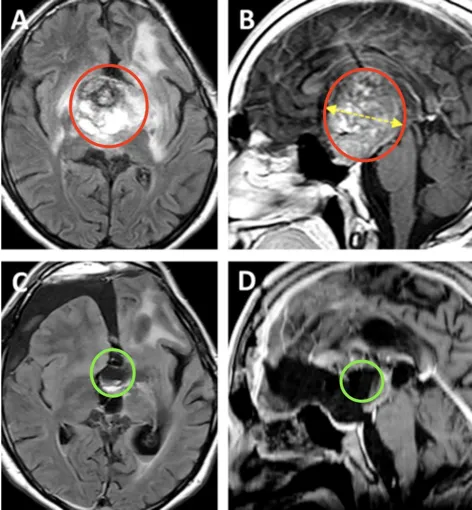

更加可怕的是,在随后的12年里,男孩的胶质瘤复发并在不断生长着,直到他长成一名16岁少年,肿瘤体积竟足足有68.1mm³,深度达到44.4mm!如此巨瘤,已经让少年苦不堪言,更何况他还出现了全垂体功能减退和严重的左侧视力障碍,几乎等同于失明。

术前情况:MRI显示鞍区、丘脑巨大肿瘤,归类为Bcentral病变的复发性毛细胞星形细胞瘤,侵犯累及左侧海马旁回和侧脑室的上部。肿瘤体积达68.1mm³,其深度为44.4mm,侧面角为21.9°。

术后情况:术后MR提示肿瘤几乎全切,两个大脑前动脉A2断动脉血管区域灌注正常,视交叉和视神经束、垂体柄和下丘脑保持原样。